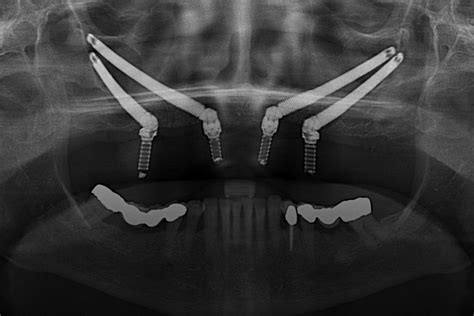

Antes de iniciar el proceso para la colocación de un implante cigomático es necesario que el dentista realice una evaluación física para conocer la salud bucal del paciente. Para complementar el diagnóstico y planificar el tratamiento adecuado, el especialista solicitará imágenes, como radiografías o tomografías, para verificar la cantidad y calidad del hueso.

Rehabilitación completa superior con implantes cigomáticos

La rehabilitación de los maxilares de los pacientes con poco hueso generalmente se realiza mediante la colocación de dos o cuatro implantes cigomáticos y de dos a cuatro implantes convencionales en la región anterior. Buen post-operatorio. Mayor tasa de éxito. Prótesis inmediata.